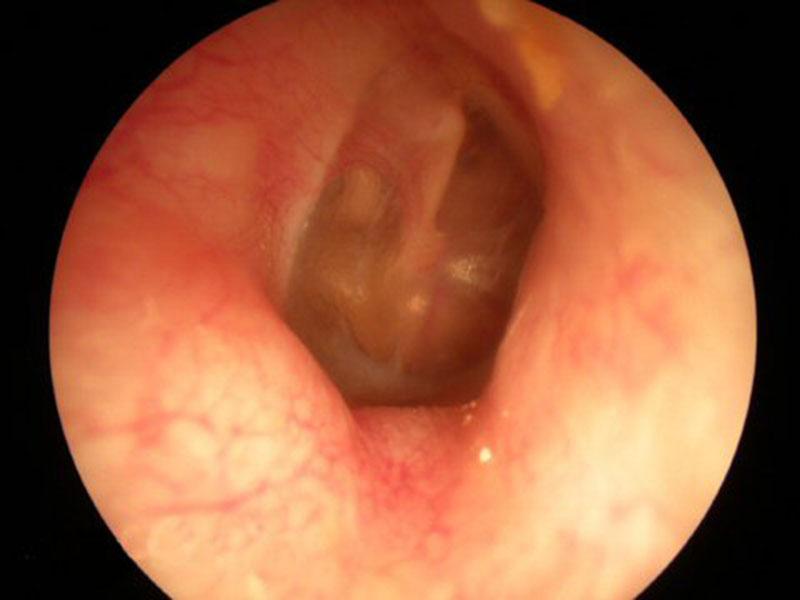

| Отомикоз | Грибковое поражение кожи слухового прохода и/или барабанной перепонки. | Зуд, ощущение заложенности уха, выделения из уха (часто черные, серые или желтые), снижение слуха. |

| Серная пробка | Скопление ушной серы в слуховом проходе, приводящее к его обструкции. | Ощущение заложенности уха, снижение слуха, шум в ухе, иногда боль или головокружение. |

Отомикоз

Часто причиной воспаления наружного уха становятся грибковые инфекции. Наиболее распространённой формой является отомикоз, который в основном поражает внешнюю часть уха, хотя иногда грибок может локализоваться и на внутренних стенках.

Воспалительные процессы развиваются быстро и неожиданно, а первым признаком заболевания является зуд и выраженное жжение в ухе.

Затем появляются выделения из слухового прохода, а наружная часть уха значительно отекает и увеличивается в объёме. Кожа в этот период становится сухой и может покрываться наростами.